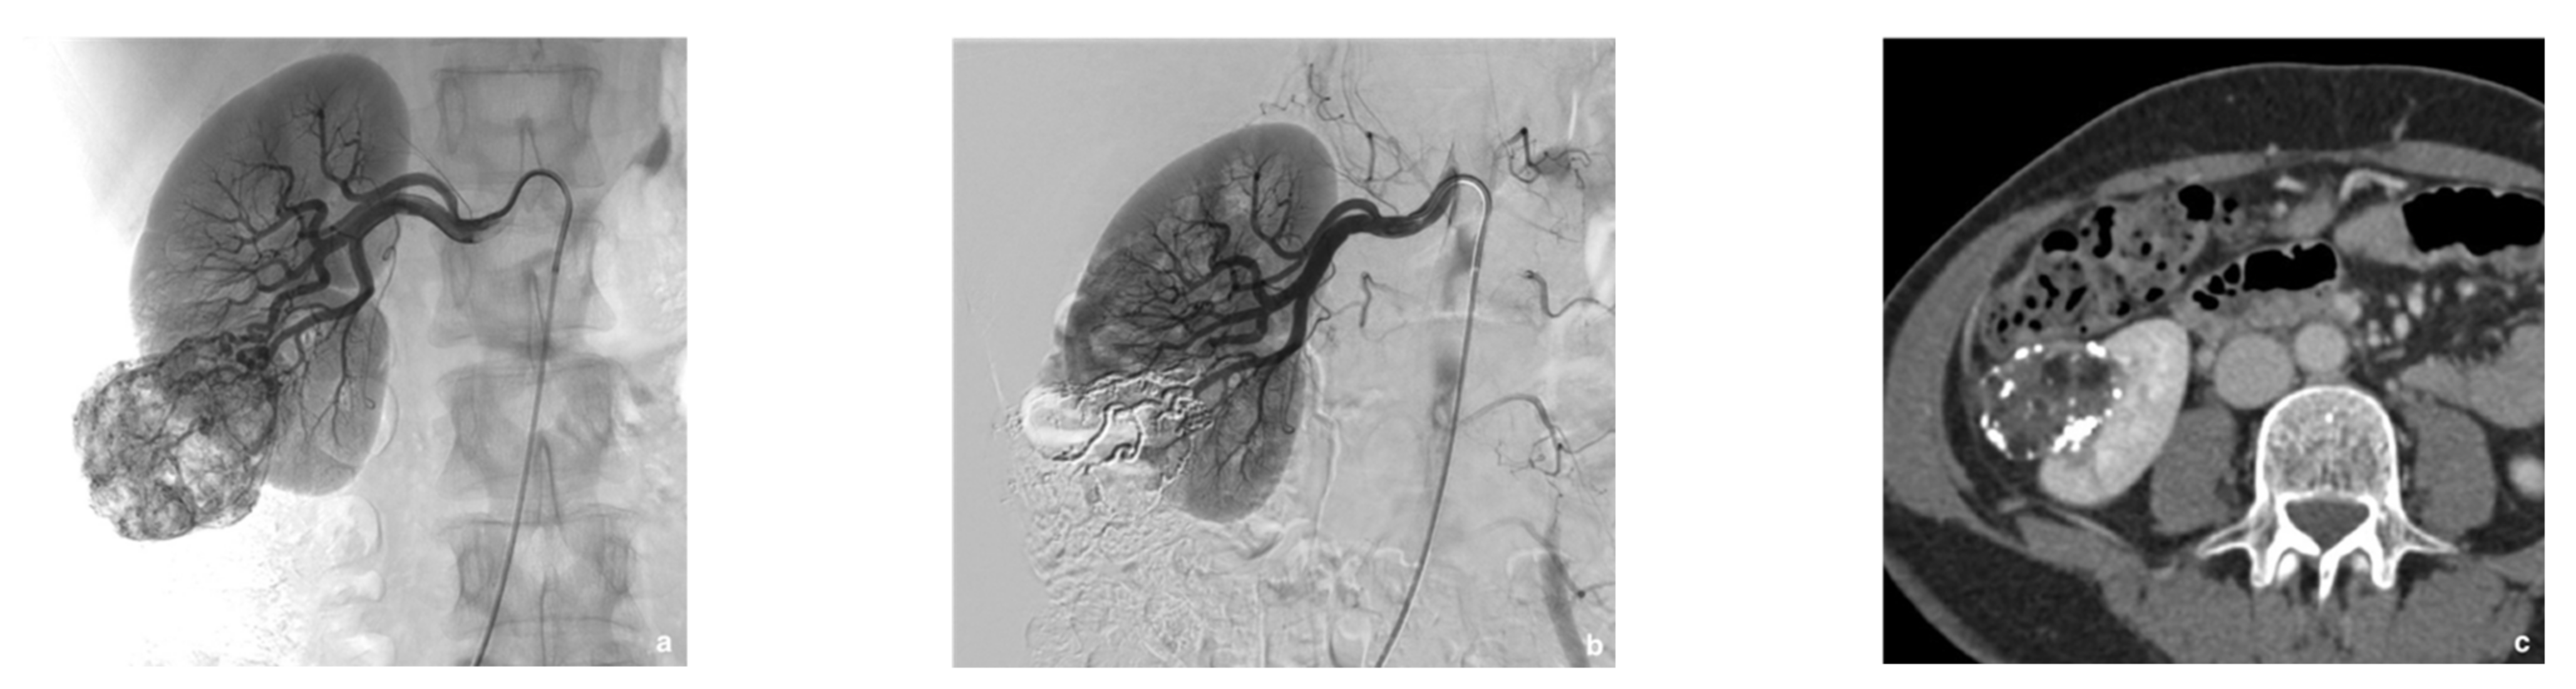

2.3. Selective Arterial Embolization (SAE)

3.2. Selective Arterial Embolization (SAE)